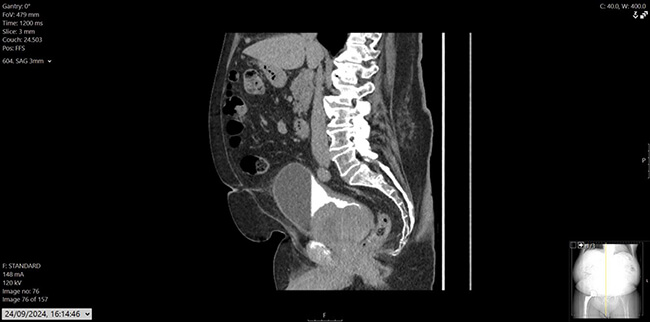

Figure 3: CT urogram, sagittal.